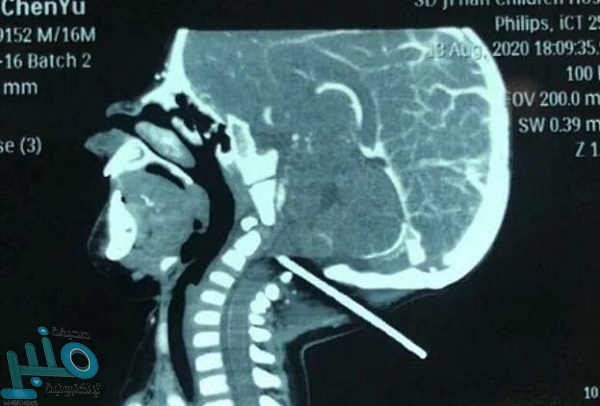

وكان الرضيع البالغ من العمر عاماً واحدًا، سقط إلى الوراء على قضيب معدني مثبت بفتحة غطاء، مما تسبب في اختراق القضيب الجمجمة من الخلف؛ حسبما ذكرت صحيفة ”ديلي ميل“ البريطانية.

وذكر التقرير، أن الطفل نقل على الفور إلى أحد المستشفيات فى مدينة جينان بمقاطعة شاندونغ، وكشف عن استقرار حالة الرضيع بعد خضوعه لعملية استغرقت ساعة، استطاع خلالها الفريق الطبي إزالة القضيب الحديدي من رأسه.

وقال الدكتور وانغ جوانغ مينغ رئيس قسم جراحة الأعصاب في مستشفى الأطفال، إن حالة الطفل كانت حرجة وقت حضوره، وبفحصه وجدوا أن القضيب كان على بُعد خمسة ملليمترات من ثقب الأوعية الدموية، مما قد يسبب نزيفًا يهدد حياته، لكن سارت الأمور على ما يرام ونجحت العملية الجراحية، ونجا الطفل.